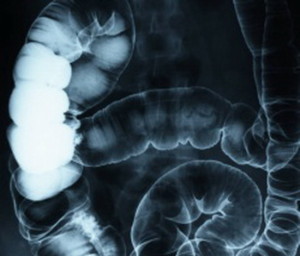

Si chiama ecoendoscopia la nuova speranza per i pazienti affetti da tumore all’apparato digerente: la combinazione fra ecografia ed endoscopia permette infatti di stabilire con esattezza il livello di stadiazione della neoplasia che, se in fase iniziale, viene immediatamente asportata per via endoscopica, risparmiando cosi’ al malato sia un piu’ impegnativo intervento chirurgico, con conseguente asportazione totale, sia il successivo trattamento chemioterapico. Da sei mesi, l’Unita’ Operativa di Gastroenterologia ed Endoscopia digestiva dell’Ausl di Forli’, diretta dal prof. Enrico Ricci, si e’ aggiunta ai pochi centri in Italia che praticano tale metodica.